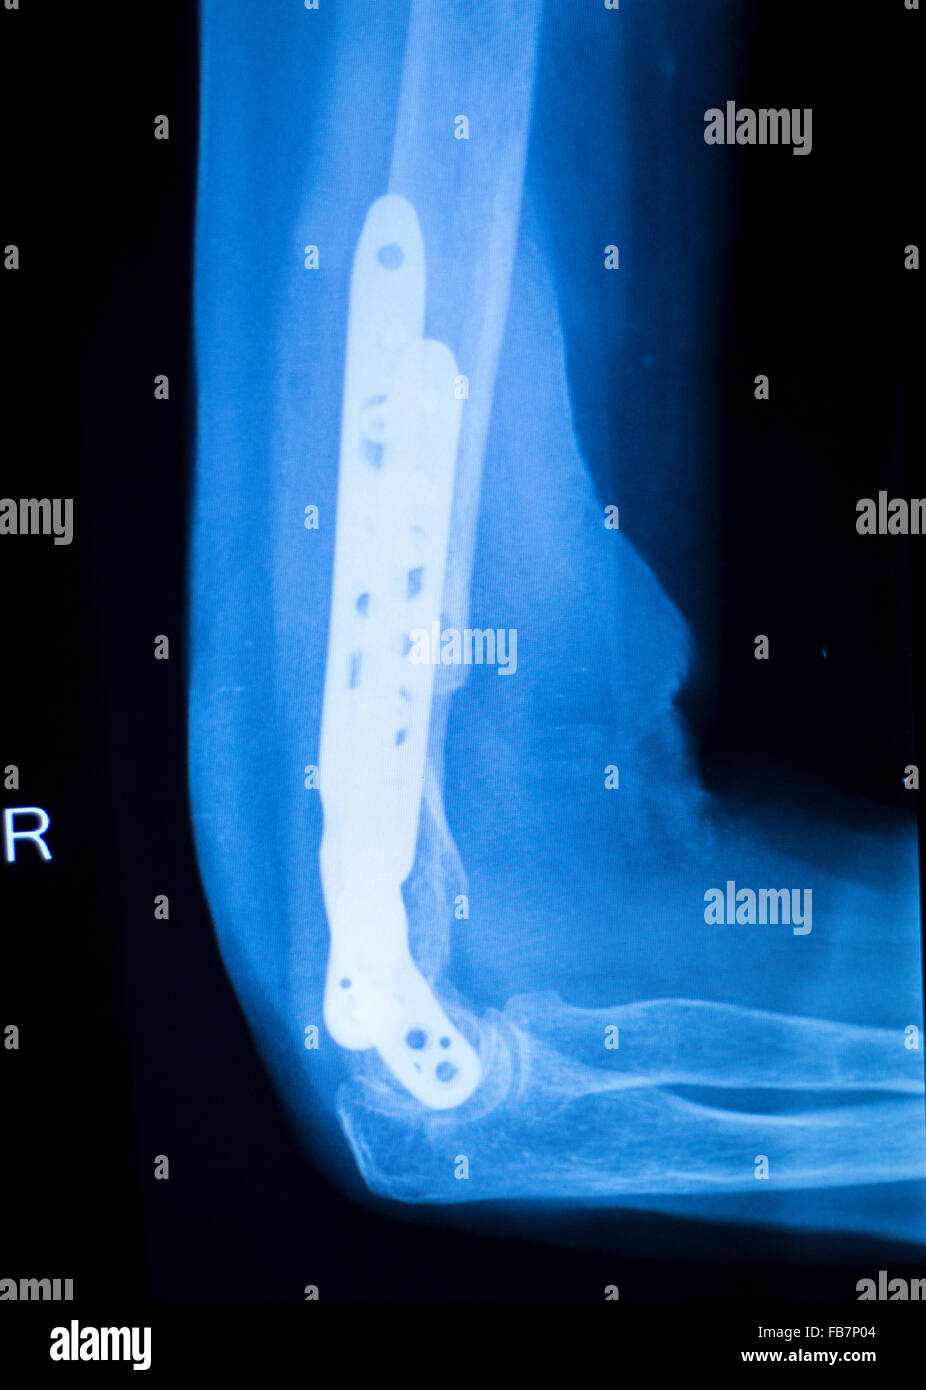

Othopedics and Traumatology surgical implant arm and elbow xray test Elbow Surgery Plate And Screws elbow, putting the fracture fragments back in their normal position, and holding them there with some type of fixation. The system features the hexalobe screw system with. this might be done with special screws, plates, wires, or nails that the surgeon places inside the bones to fix them in the correct. The pieces are then put together and. Elbow Surgery Plate And Screws.

From www.alamy.com